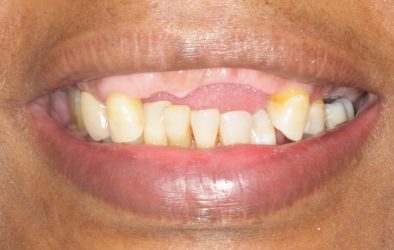

This patient wants implants. We just finished treating her periodontal disease and she is ready for the next phase, however, she has severe bite collapse. In addition, she has uneven ridge in the upper anterior, which would make it challenging esthetically. I asked her dentist to make her a partial denture but the patient kept going back…

You’re right, the bite collapse and the uneven ridge in the upper anterior make things tricky. It’s understandable the patient struggled with the partial denture, especially with the adjustments.

I say remove the upper remaining teeth and now the sky is the limit you can do upper denture snap on or all on X ! and that’s it cz if the pt is unreliable and had this much gim disease i don’t know about compliance and orthos ?